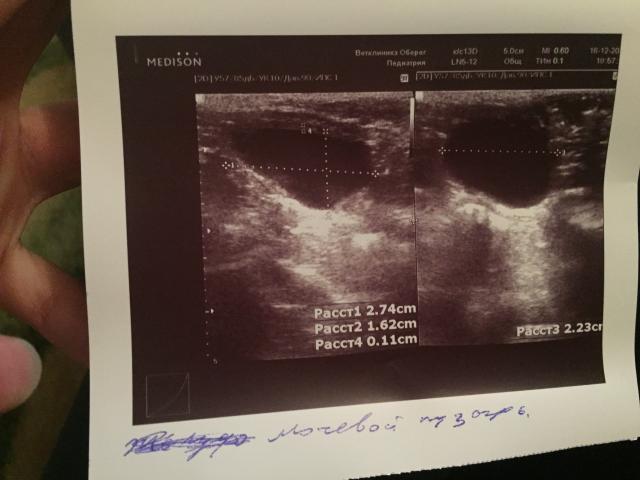

Если можно, то немного подробнее. На основании чего вам поставили такой диагноз, только на основании проведенного УЗИ? Может быть, собаке брали какие-то анализы? Если да, то выложите, пожалуйста, здесь их результаты. Если только данные УЗИ, то это разговор ни о чем (я имею ввиду панкреатит). Гастрит по данным УЗИ вообще не ставят.

К сожалению, ничего не могу рассмотреть. Попробуйте сами прочесть описание с фото. Если сможете, сделайте снимок более качественным. Или можно снять крупнее по частям. Может быть, тогда буквы будут видны более четко.

Спасибо, фотографии четкие. Я все прочитал. Как я и думал, там и "не пахнет" никаким гастродуоденитом, а тем более, панкреатитом.